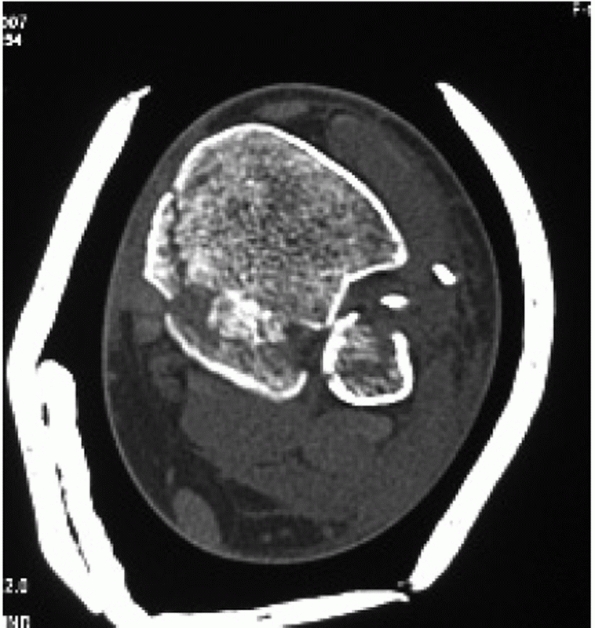

of ankle fractures is limited. The CT scan provides cross sectional

information, which clarifies the relationship of the tibia and fibula

at the mortise, the fit of the talus within the mortise, as well as

information regarding possible associated injuries to the peroneal or

posterior tibial tendons.191,192,193,217

The greatest asset of CT scans in the setting of ankle fractures is to

diagnose tibial plafond impaction injuries, posterior malleolar

fractures, and

associated injuries of the talus.123,147,148

The size of the posterior malleolar fragment, which determines

operative treatment, is notoriously poorly quantified on plain films

with low interobserver and intraobserver reliability. The CT scan is

clearly useful in cases where the size of the posterior malleolus is

questionable.60 Other uses for CT scans of the ankle are evaluation of chronic ankle sprains and subtalar injuries.136,137